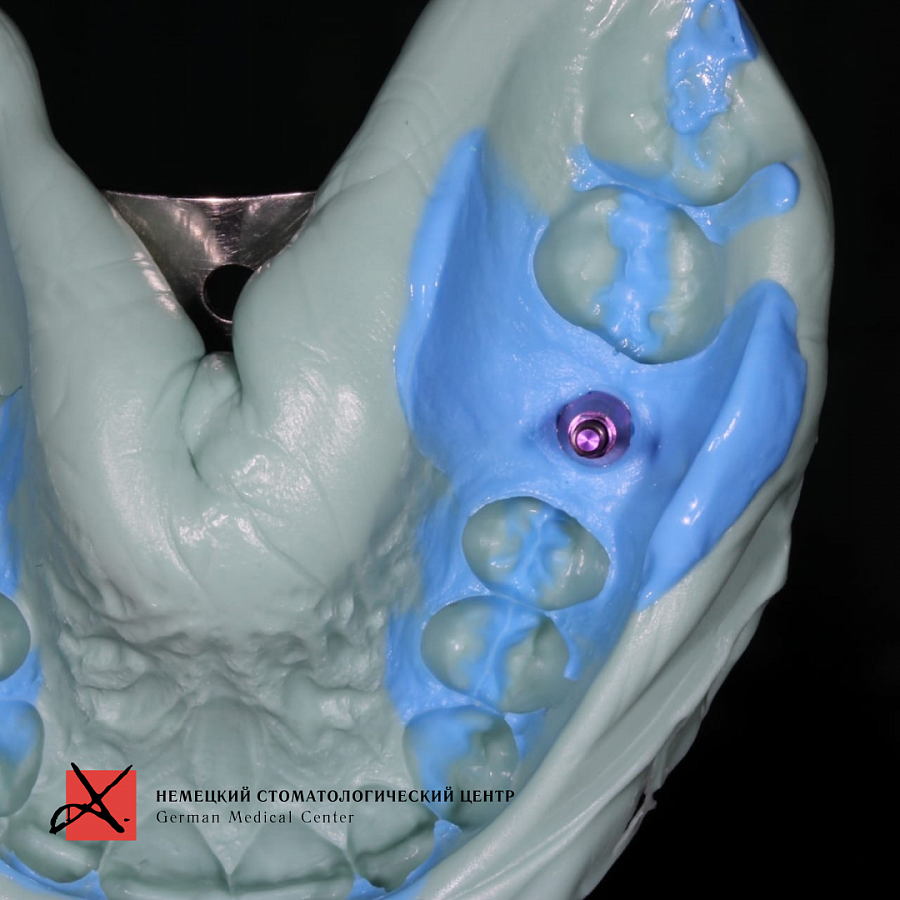

Провели костную пластику с последующей имплантацией. Материал для пластики - Geistlich Bio - Oss ( Био Осс ) - натуральный костнозамещающий материал, покрытый мембраной. Через 6 месяцев провели имплантацию и далее протезирование.